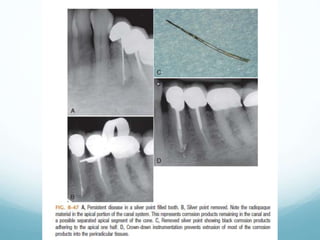

Removal of Silver Point

It is apart of history, it has been used in the past

because of their ease of handling and placement.

Not used now days as it corrode with time ,loss of

the apical seal and the the corrosion products are

toxic and irritate to apical tissue.